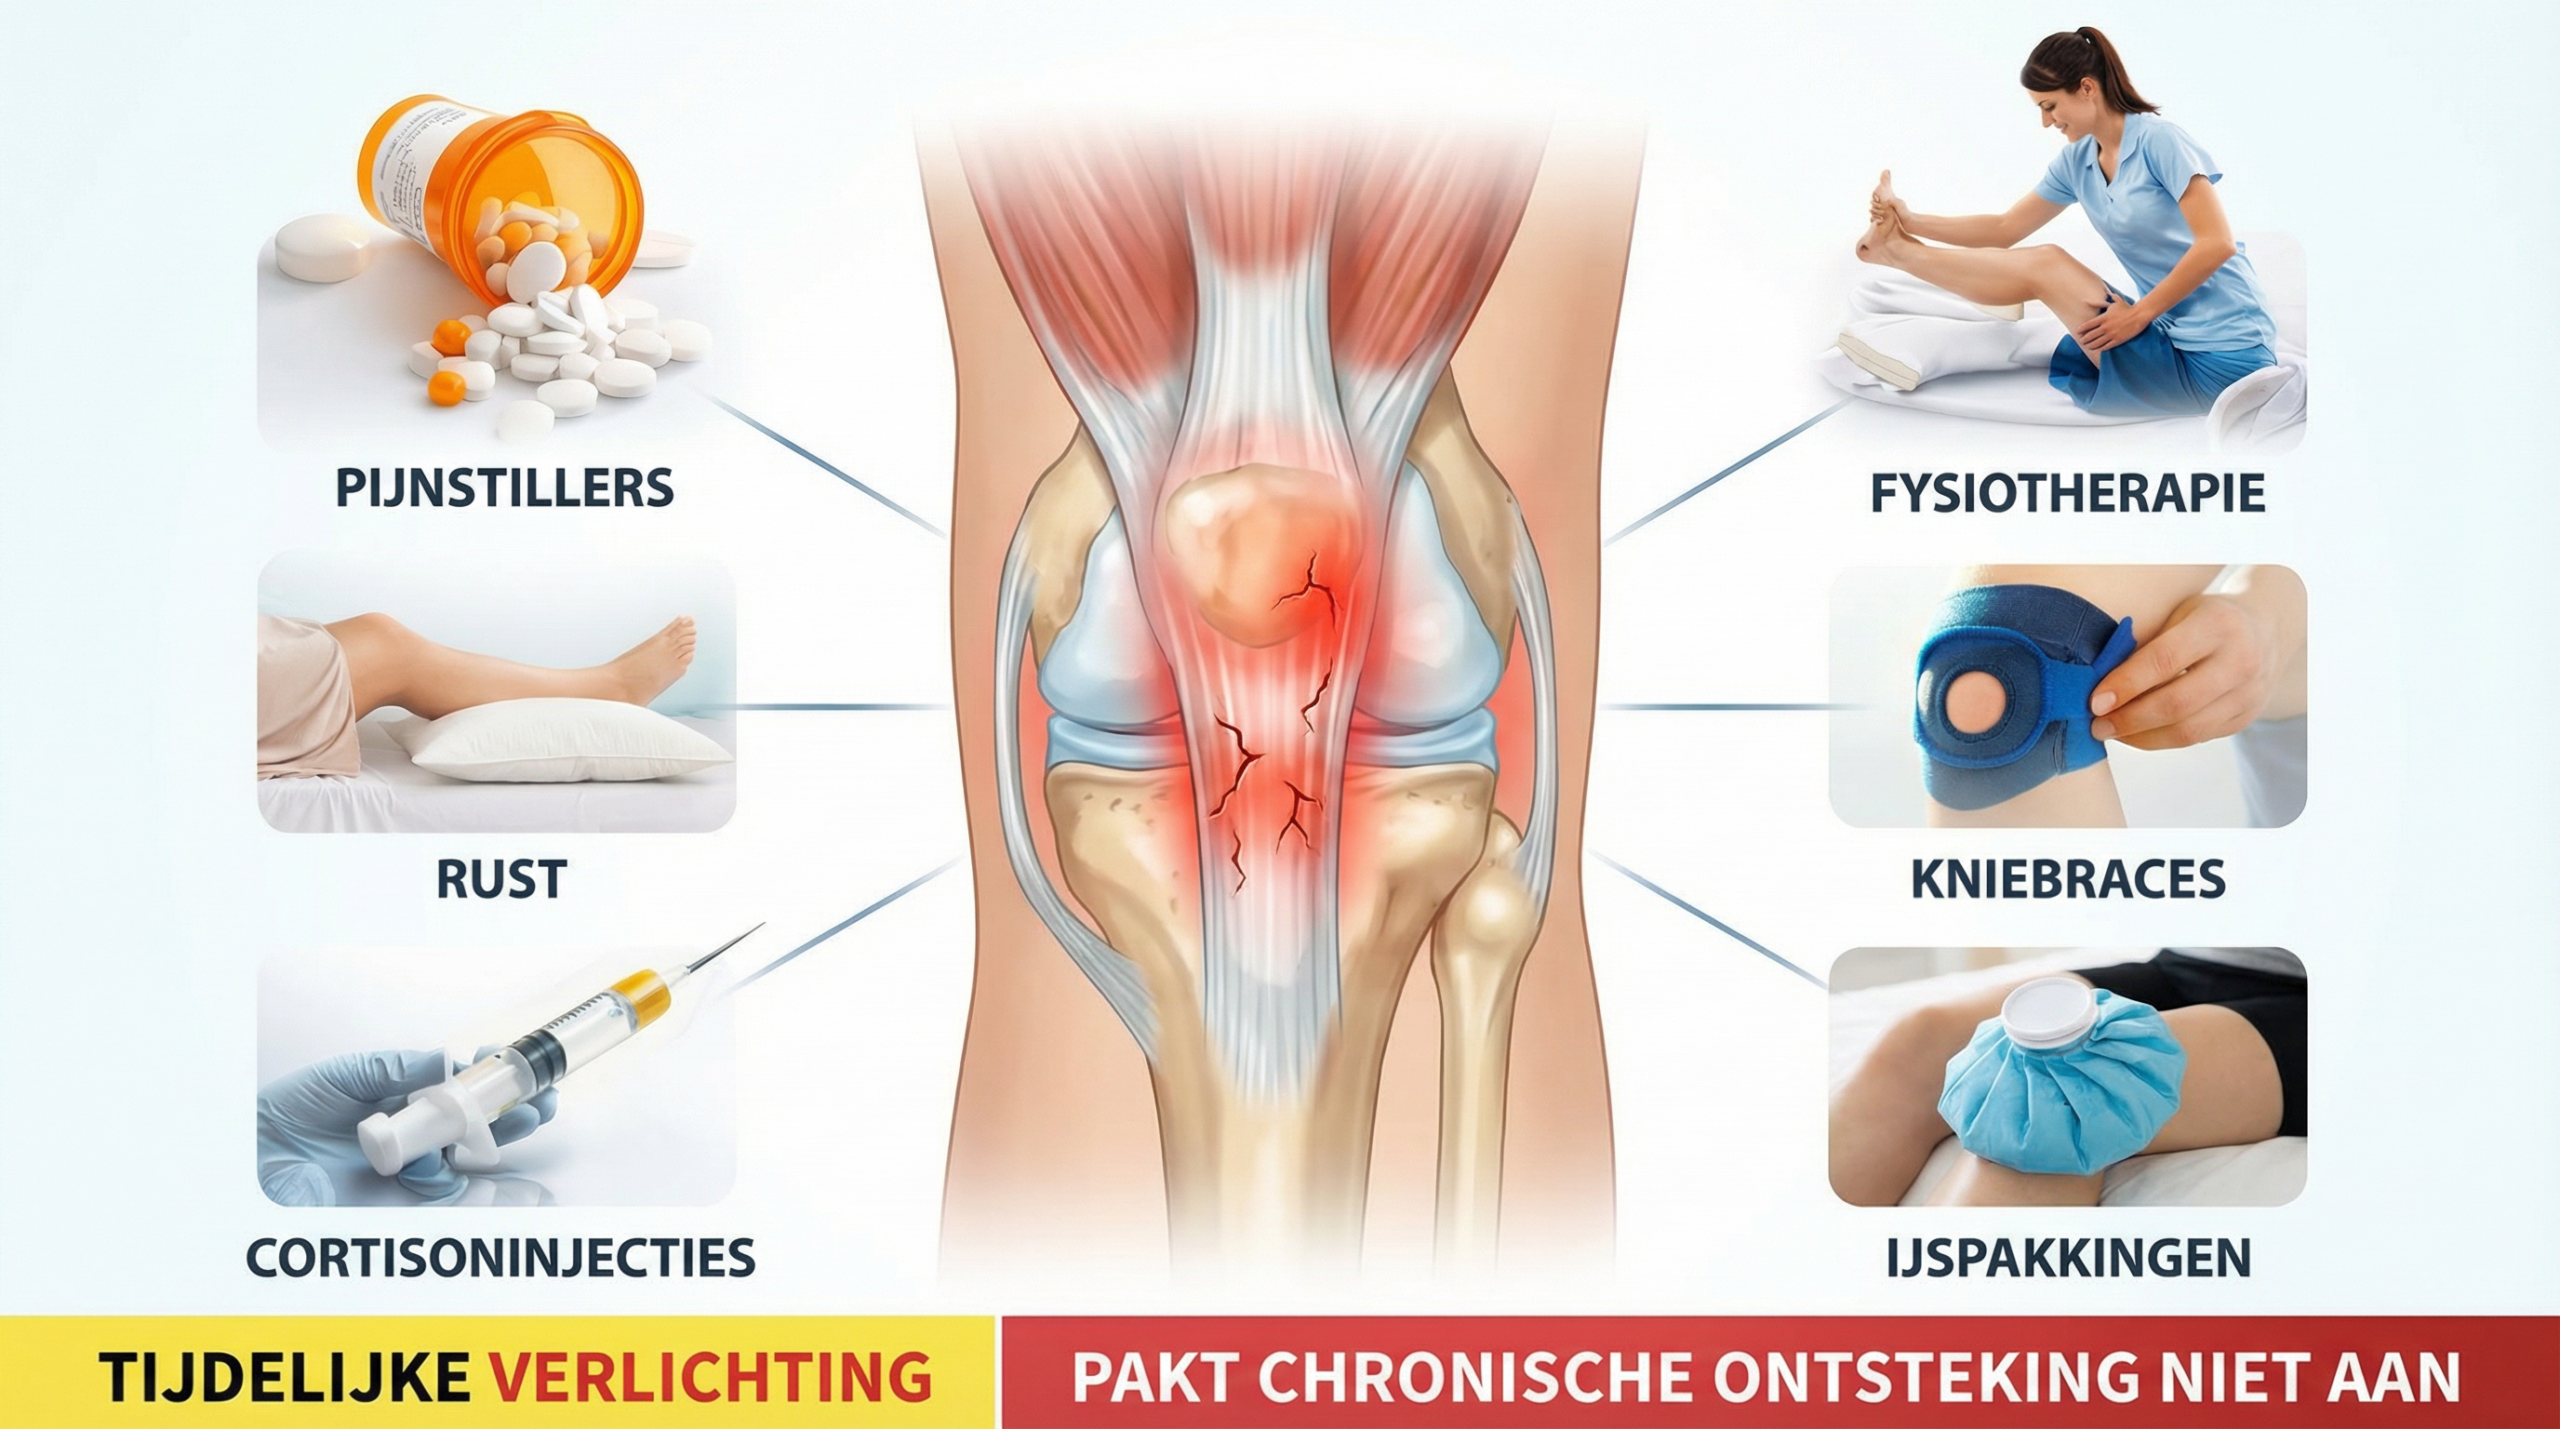

Waarom falen bestaande oplossingen dan?

"Maanden van fysiotherapie, een kniebrace, twee injecties en dozen vol pijnstillers. Elke keer een korte verlichting en daarna weer hetzelfde liedje. Zodra ik weer begon te sporten, was de kniepijn terug. Ik voelde me vastgelopen en begon te geloven dat ik nooit meer pijnvrij zou bewegen."

Het probleem?

Al deze oplossingen behandelen het symptoom.

Niet de oorzaak.